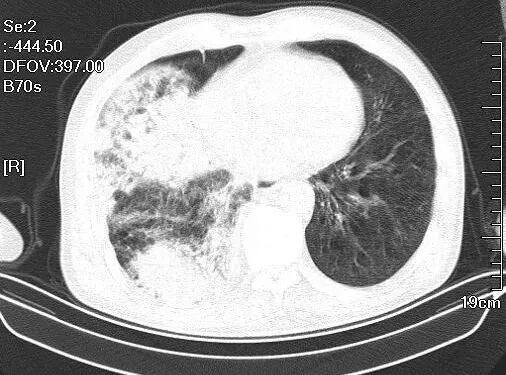

由于海西州人民医院没有急诊床边心脏B超等辅助检查设备,唐小平和内科卓玛措主任跟病人家属充分沟通,告诉家属目前进行肺部增强CT的必要性以及检查的风险,家属充分考虑后同意进行肺部增强CT检查。团队立即带着监护仪和抢救设备陪护病人进行了肺部增强CT检查,检查结果提示肺动脉没有明显充盈缺损,这就意味着可以初步排除肺栓塞。

(保大爷增强CT片子)

但是仅仅24小时左右,保大爷右侧胸腔积液大量增加,几乎填满了右半个胸腔,而且右肺的渗出病变也大面积增加。胸腔穿刺继续查明病因,才能进行及时有效治疗。通过床边B超的准确定位,保大爷在吸氧和监护下,顺利进行了胸腔穿刺,接上引流管,引流出来的胸水是浑浊的,唐小平初步诊断是急性脓胸,这意味着感染,心里禁不住后怕,如果没有当初说服拒绝有创检查的家属进行及时胸腔穿刺引流的话,保大爷接下来的感染情况将不堪设想。